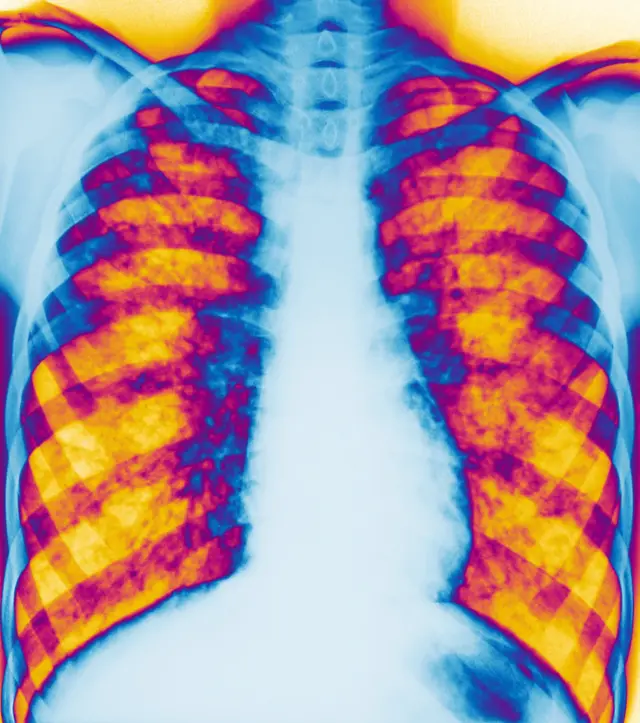

Ova 30-godišnja kopirajterka se bori sa cističnom fibrozom, naslednom genetskom i smrtonosnom bolešću, i to je jedini način da izgura dan, pošto njena pluća rade sa 25 do 35 odsto kapaciteta, a kao posledica ovog oboljenja javili su se osteoporoza i dijabetes.

Kod većine obolelih javljaju se problemi sa plućima, od kojih strada 96 odsto preminulih sa ranije dijagnostifikovanom cističnom fibrozom, ali bolest napada i jetru, bubrege, pankreas, kosti i druge organe, kaže Predrag Minić, specijalista za ovo oboljenje sa Instituta za majku i dete u Beogradu.

Bolest uglavnom napada pluća i organe za disanje od čega umire 94 odsto preminulih od cistične fibroze, a četiri odsto strada od bolesti jetre, rekao je doktor Predrag Minić na Okruglom stolu Udruženja za pomoć i podršku osobama sa cističnom fibrozom Srbije.